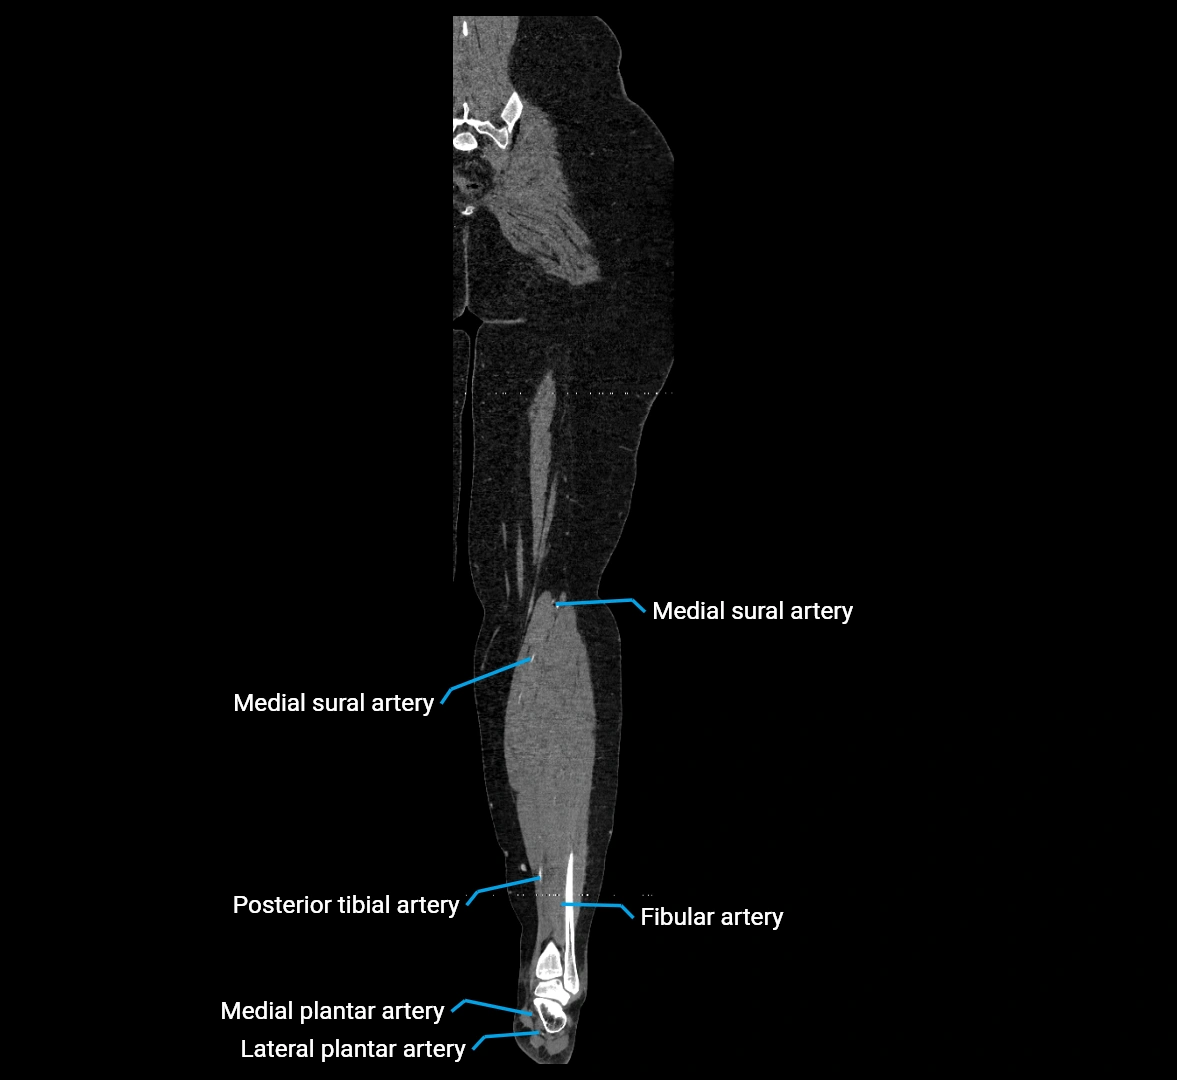

CT images

image

Contrast-enhanced CT (CTA):

• Gold standard for abdominal aortic imaging

• Provides excellent detail of lumen, wall, aneurysm, thrombus, and branch vessels

• Multiplanar and 3D reconstructions help in aneurysm measurement, stent graft planning, and dissection evaluation